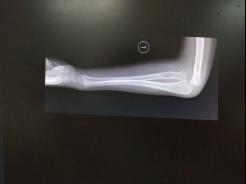

儿童陈旧性孟氏骨折

术后肘关节侧位片

儿童陈旧性孟氏骨折,术前桡骨小头陈旧性脱位,经截骨矫形治疗后1个月,桡骨小头已复位,患儿肘关节屈伸功能(1-2图),前臂旋转功能(3-4图)正常